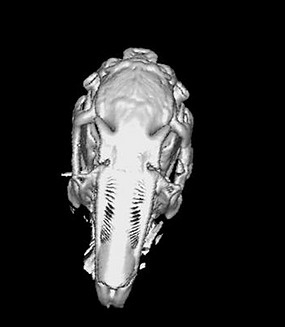

Figure 10: Hydroxyapatite implant – coronal section CT appearance at 1 month postoperatively. Increased bone density is noted inside the implant, but inhomogeneous, with areas of fibrovascular tissue

DiscussionsThe CT analysis performed one month postoperatively shows values of the density of the hybrid nanostructured hydroxyapatite implant at the level of the bone defect lower than the bone density of the animal model, but they increase progressively at 2 months postoperatively. In terms of density, this is above the density of fibrous tissue but below the bone density of the animal model. The nanostructured hydroxyapatite implant at 1 month postoperatively presents good density but in two cases the persistence of a cleavage plane between the implant and the bone is noted, demonstrated by the presence of a fibrovascular tissue with low density (HU=40). In one subject the presence of a large cleavage plane is observed, the explanation of this phenomenon could be related to the large difference between the density of the fibrovascular tissue and the density of the bone cortex (HU=1120) which makes the visibility of the fibrovascular tissue interpreted as a lack of substance. The nanostructured hydroxyapatite implant at 2 months postoperatively presents on CT examination a density closer to the bone density of the animal model and the absence in most cases of the cleavage plane, a clear sign of the integration of the implant into the bone tissue.

Figure 18: Rabbit1-3D CT bone reconstruction. Nanostructured hydroxyapatite implant at 1 month postoperatively (arrow). The persistence of a cleavage plane between the implant and the bone is noted, demonstrated by the presence of a low-density fibrovascular tissue (HU=40)